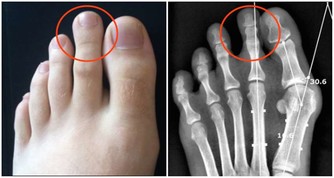

6. 你會感到頭暈、暈眩

鉀的工作任務之一是保持神經系統健康。

當你沒有足夠的鉀時,手臂和腿部會感到刺痛,並且會感到麻木。

而鉀的大幅下降,也會減慢你的心跳,讓你感覺頭暈目眩,好像你會隨時暈倒似的。